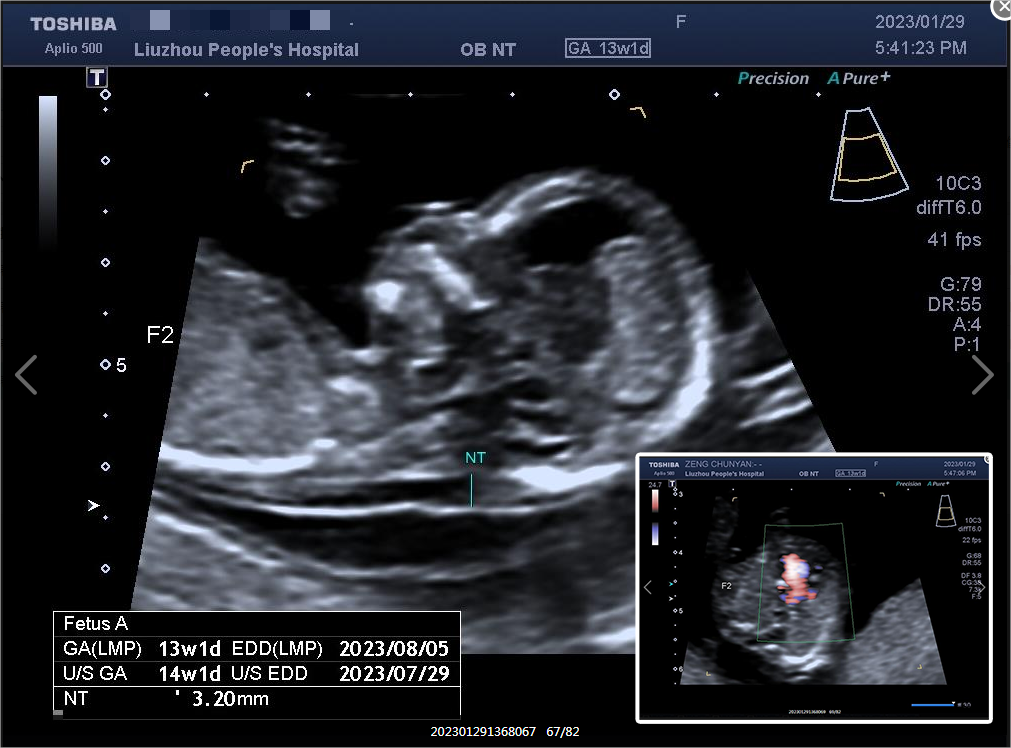

懷上了雙胞胎,原本是一件開(kāi)心的事情,但曾女士一家近期卻十分焦慮。原來(lái),曾女士在妊娠13周產(chǎn)檢超聲NT檢查時(shí)發(fā)現(xiàn)兩個(gè)胎兒其中一個(gè)存在嚴(yán)重致死性畸形,焦慮感頓時(shí)籠罩在曾女士周?chē)?/span>

“確實(shí)沒(méi)有必要因?yàn)橐粋€(gè)胎兒發(fā)育異常就終止妊娠,我們可以盡全力幫助您保留住正常胎兒?!比~云飛醫(yī)生耐心地解釋?zhuān)簷z查發(fā)現(xiàn)胎兒為單腔心,屬于我們國(guó)家明確的重大致死致殘出生缺陷疾病種類(lèi)中的一種,從優(yōu)生優(yōu)育考慮出發(fā),在孕28周前診斷單腔心畸形的胎兒,應(yīng)建議中止妊娠。如雙胎中一胎為重大致死致殘出生缺陷、但另外一胎發(fā)育健康,經(jīng)醫(yī)生充分告知后,在尊重雙親意見(jiàn)、符合倫理原則的前提下,可以選擇進(jìn)行減胎,以保證另外一個(gè)胎兒的健康。